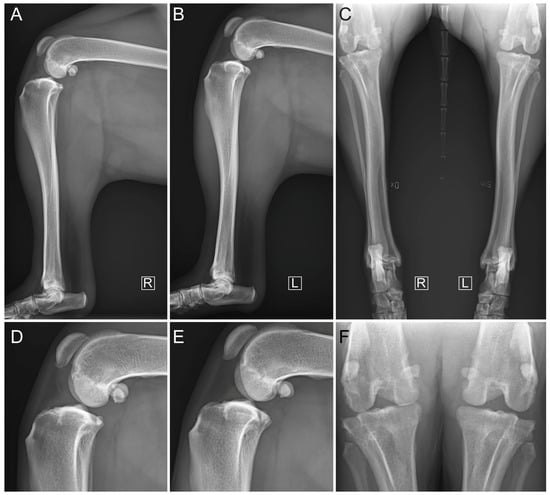

2.3. Diagnostic Imaging under Anesthesia

3. Results